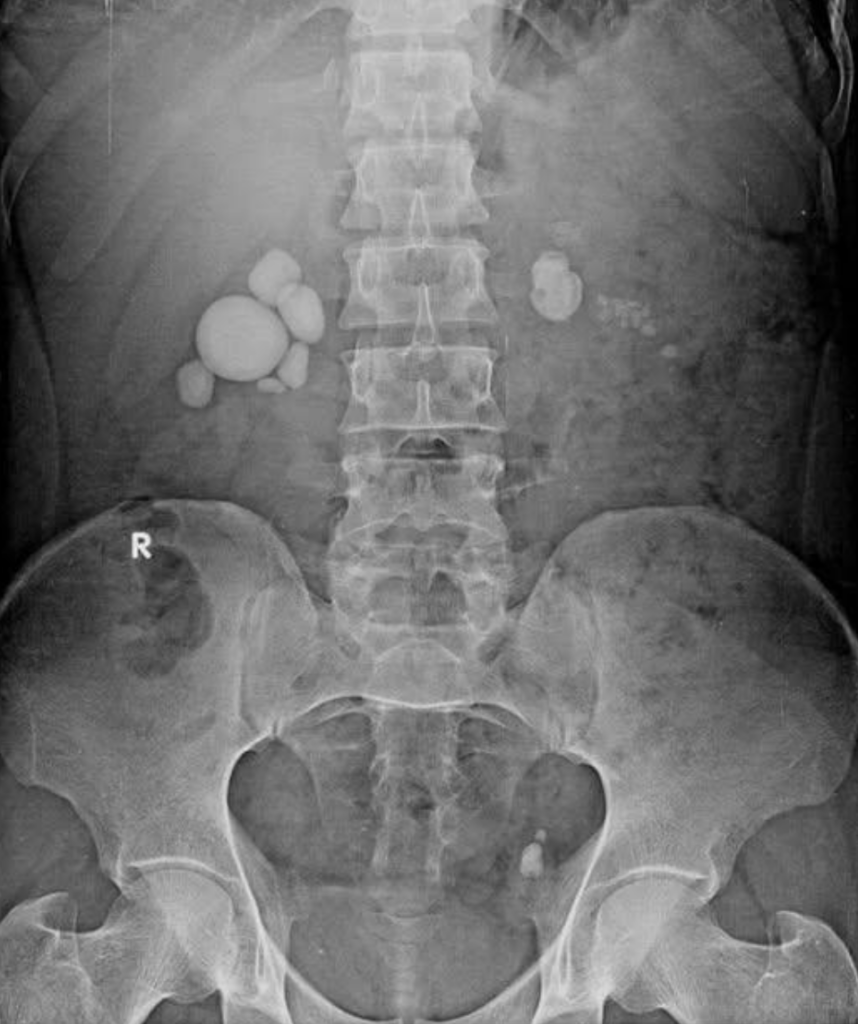

Existujú rôzne typy obličkových kameňov, ktoré sa líšia podľa svojho zloženia a príčin vzniku.

Tieto kamene sa odlišujú nielen podľa príčin vzniku, ale aj priebehom, diagnostikou (RTG) a hlavne biochemickým rozborom.

Diagnostika močových kameňov zahŕňa kombináciu hodnotenia príznakov, fyzikálneho vyšetrenia a zobrazovacích či laboratórnych testov.